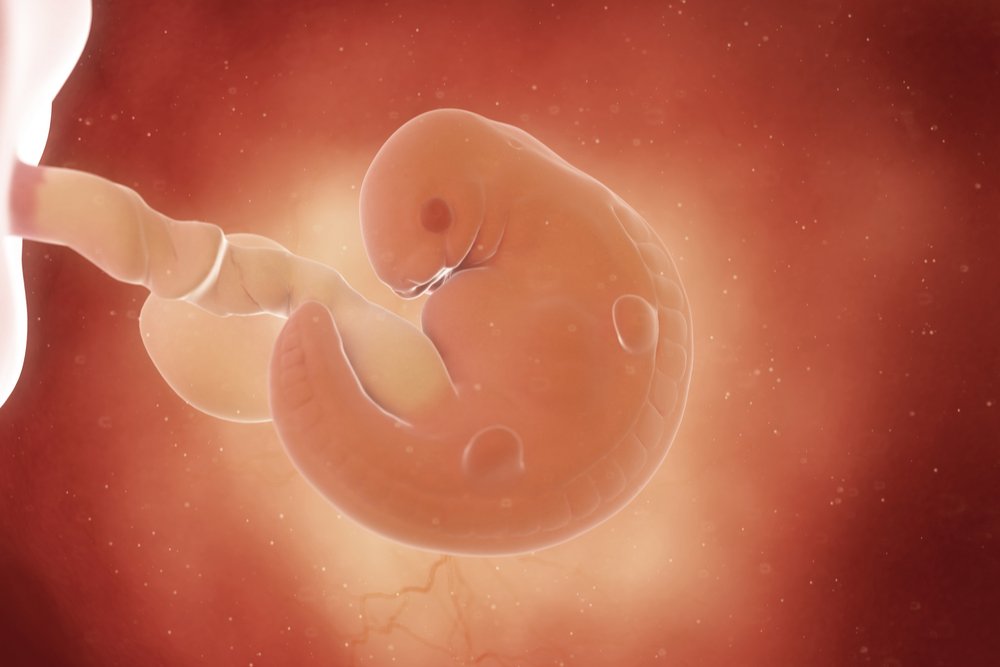

Развитие эмбриона: Что происходит на 3 неделе беременности

Раздел: Фотопанорама